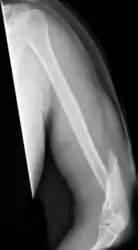

Middle

Middle fractures are usually caused by either physical trauma or falls. Physical trauma to the humerus shaft tends to produce transverse fractures whereas falls tend to produce spiral fractures. Metastatic breast cancer may also cause fractures in the humerus shaft.[12] Long spiral fractures of the shaft that are present in children may indicate physical abuse.[5]

Definitive diagnosis of humerus fractures is typically made through radiographic imaging. For proximal fractures, X-rays can be taken from a scapular anteroposterior (AP) view, which takes an image of the front of the shoulder region from an angle, a scapular Y view, which takes an image of the back of the shoulder region from an angle, and an axillar lateral view, which has the patient lie on his or her back, lift the bottom half of the arm up to the side, and have an image taken of the axilla region underneath the shoulder.[9] Fractures of the humerus shaft are usually correctly identified with radiographic images taken from the AP and lateral viewpoints.[12] Damage to the radial nerve from a shaft fracture can be identified by an inability to bend the hand backwards or by decreased sensation in the back of the hand.[5] Images of the distal region are often of poor quality due to the patient being unable to extend the elbow because of pain. If a severe distal fracture is suspected, then a computed tomography (CT) scan can provide greater detail of the fracture. Nondisplaced distal fractures may not be directly visible; they may only be visible due to fat being displaced because of internal bleeding in the elbow.[7]

Fractures of the humerus shaft are most often uncomplicated, closed fractures that require nothing more than pain medicine and wearing a cast or sling. For midshaft fractures up to 12 weeks may be required for healing.[17]